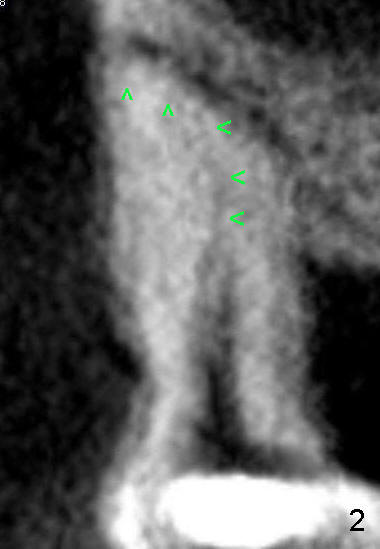

打开髓腔,MB根管还是通不到根尖,突然意识到自己有个大缺点:看片不认真。不得不脱下手套,走到办公室,关掉电灯,在暗光下,再次研究MB根以及根管特点:它们都向颊侧弯曲(图二箭头)!研究CT另外一个断面(图三)发现MB根和根管也往远中弯曲。方向明确后,预先弯曲扩大针,尽管笨手笨脚,最终目的还能达到,图四显示主牙胶尖插入:MB: